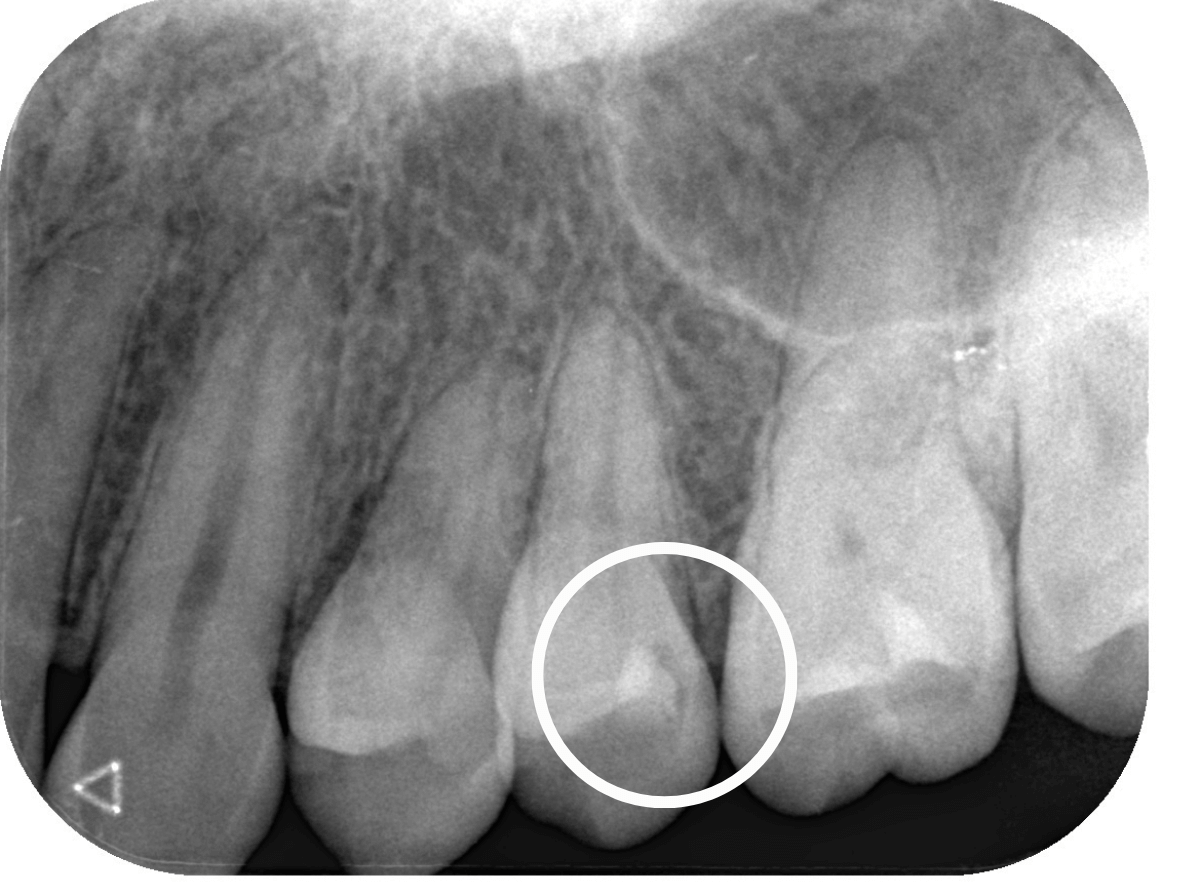

Case.9 レジンの中で大きく広がった虫歯

他の歯の治療希望で来院された患者さんです。

検査をすると、他の場所にも大きな虫歯が見つかりました。

レジン(つめもの)の下の虫歯で、この写真では、わかりづらいですが、中で広がっています。

レントゲン写真で確認します。

レジンの下が虫歯になっているのが確認できます。